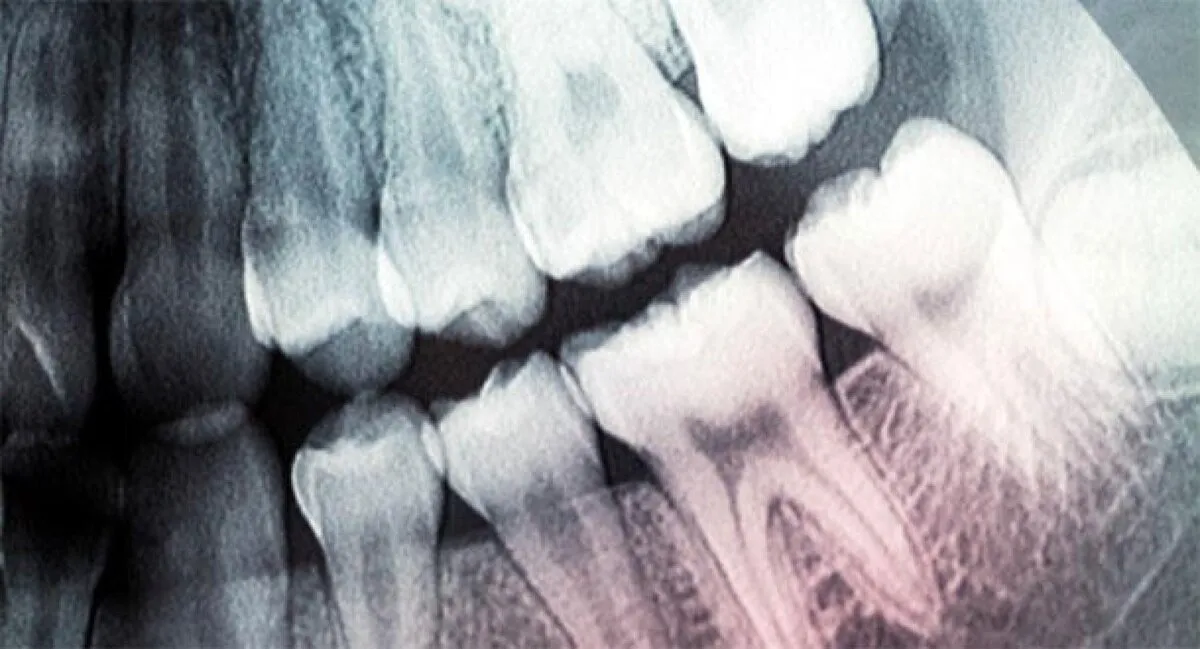

لا تنمو الأسنان مرة أخرى بمجرد أن نصبح بالغين، ولهذا السبب من المهم الحفاظ على نظافتها وصحتها قدر الإمكان.

أفادت وکالة آنا الإخباریة، وقد تم الإعلان عن بدء التجارب السريرية لعلاج محتمل لإعادة نمو الأسنان في يوليو 2024، بناء على عقود من البحث في هذا المجال. وإذا نجحت هذه التجارب، يمكن أن تكون الأدوية العلاجية متاحة بحلول عام 2030.

ويتولى فريق من معهد البحوث الطبية في مستشفى كيتانو باليابان مسؤولية التجربة، التي تستهدف الأشخاص المصابين بقصور الأسنان، وهي حالة وراثية نادرة تمنع أسنان الأطفال وأسنان البالغين من النمو بطريقة طبيعية.

وسيستهدف العلاج في البداية الأطفال الصغار المصابين بهذه الحالة، ولكن بعد ذلك، يعتقد الباحثون أنه يمكن استخدامه أيضا على نطاق أوسع - مع الأشخاص الذين يعانون من مشاكل أسنان أكثر شيوعا، مثل أمراض اللثة، على سبيل المثال.